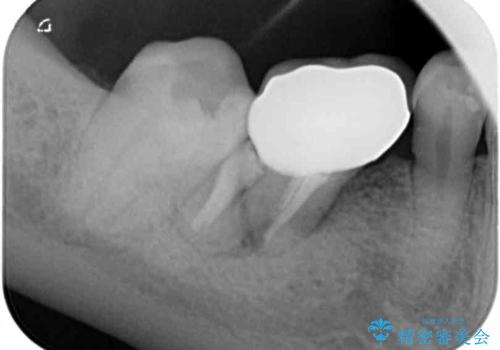

レントゲン写真より、歯根周辺に大きな病変(炎症により骨が溶けている状態)が認められたため、歯根が破折している可能性が示唆されました。

歯根が破折した歯は抜歯となるため、抜歯して病変の部分に骨が回復するのを待って、インプラントによる補綴治療を行うこととしました。

病変が大きかったことや、神経や血管が多く通る管が近いこともあり、抜歯即時埋入ではなく、骨の治癒が待ってから埋入を行う、従来の方法にてインプラント治療を行いました。